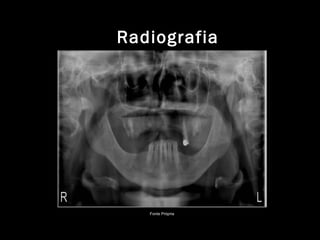

Radiografia Periapical e Panorâmica;

Radiografia

Fonte Própria

Paciente C.M.M.P brasileira, leucoderma, 50 anos de idade,

apresentou-se à Clínica CI 2 (Clinica Integrada 2) na CLIOF do

Curso de Odontologia da Faculdade Maria Milza, com o objetivo

de realizar um tratamento odontológico. Na avaliação intra oral

foi constatado a necessidade de reabilitação oral superior e

inferior. Após completo exame clínico, radiográfico e laboratorial

(Figuras 1, 2 e 3) , foi observado a necessidade de algumas

extrações dentárias com posterior regularização bilateral de

rebordo alveolar superior para que após cicatrização fosse

confeccionado uma Prótese Total para a paciente. Em região de

Mandíbula algumas restaurações serão feitas e reabilitação com

PPR (Prótese Parcial Removível).